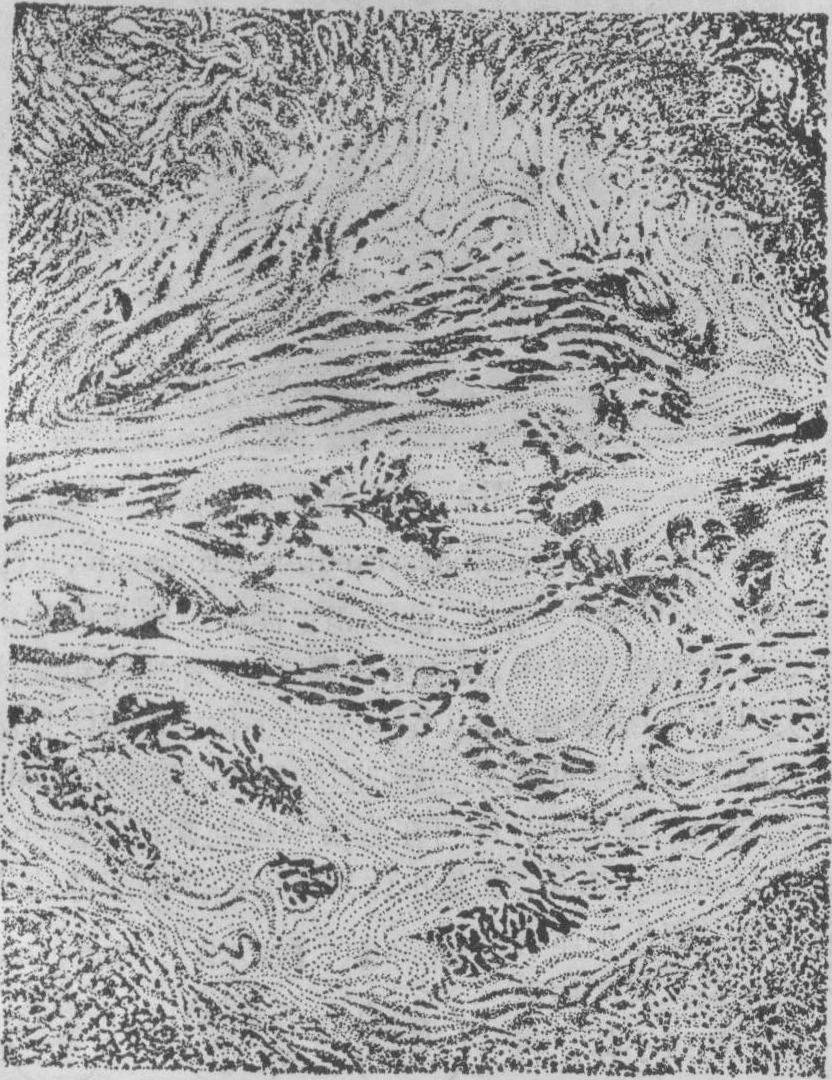

斑疹伤寒小结 立克次体进入人体后主要在血管内皮细胞内繁殖,所以小血管内皮细胞常肿胀增生,甚至阻塞管腔(血管炎),其外并有淋巴细胞等围绕。斑疹伤寒小结就是以增生的细小动脉或毛细血管为中心形成的。结节小,镜检才能看到。分布于大、小脑各处,尤其多见于大脑导水管周围,以及桥脑、延髓橄榄核等处的灰质。在皮肤、睾丸、心肌间质亦可发生,但不如脑内的小结多而明显。脑内的小结中央,毛细血管因内皮细胞肿胀增生常致管腔闭塞,周围有多数的小胶质细胞、小突胶质细胞及巨噬细胞等成分。脑内的这些小结是本病较为特殊的病变,在虱型斑疹伤寒中较蚤型中多见。

图1 脑的斑疹伤寒小结